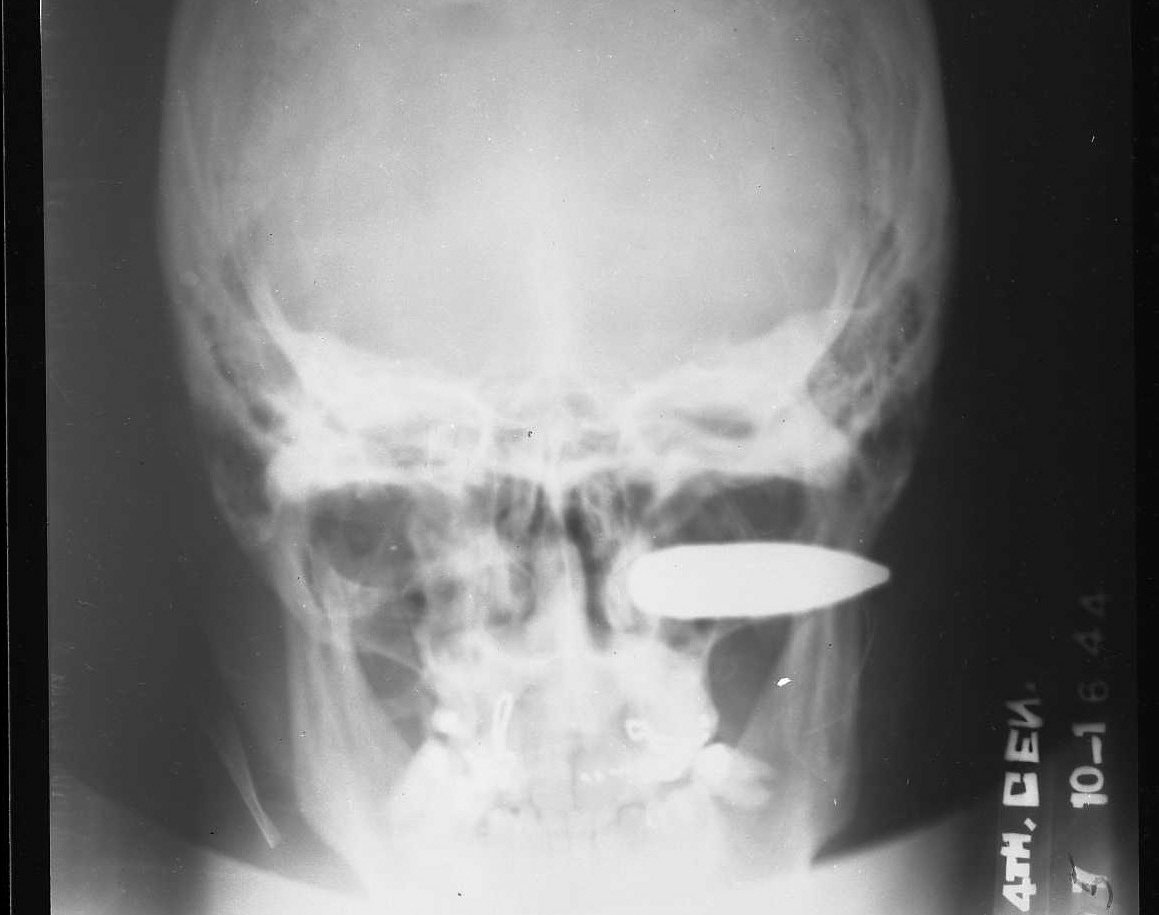

Published this month in the Journal of Trauma and Acute Care Surgery, “Gunshot wounds and blast injuries to the face are associated with significant morbidity and mortality: Results of an 11-year multi-institutional study of 720 patients” brings scientific precision to the common-sense proposition that bullets to the face are really bad.

This being a study published in a journal of trauma medicine, the goal is of the study wasn’t necessarily to figure out the cause of the injuries, but how best to treat them. To classify injuries, the doctors divided the face into three zones, as seen above. Just over a fifth of injuries hit above the brow line (zone three), while slightly more than a third of injuries fell from the nose up to the brow line (zone two), and just shy of a third of injuries feel between the chin and the base of the nose (zone one). The rest of the injuries were blasts (which tend to not fall into tidy categories) or injuries that straddled the zones. Including zone three, the forehead zone, this study showed a higher mortality rate for gunshot wounds than others which have come before.